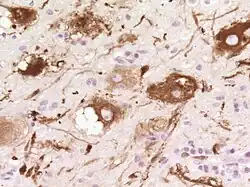

Pathologie und Histopathologie

Auf zellulärer Ebene sieht man dysplastische (hypertrophe und später blasig aufgetriebene, vakuolisierte) Purkinjezellen. Die Schichtung des Kleinhirns ist umgekehrt (invertiert) und die Körnerzellschicht ist weitgehend aufgelöst.